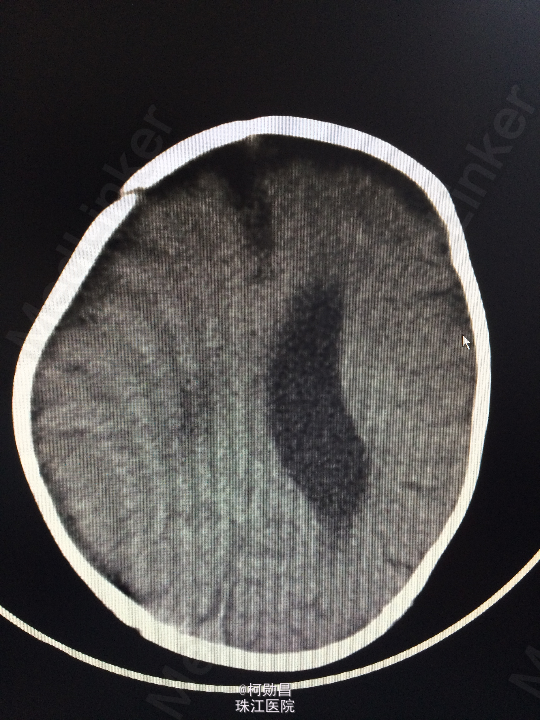

主诉:发热10天,抽搐3天 病史:患儿出生后8个月,因“发热10天,抽搐3天”入院,入院时体温39.3℃,神志不清,反应差。四肢肌张力增高,以双上肢肌力增高明显。病理征未引出。

查体:神志不清,四肢肌力增高 辅助检查:头颅CT提示脑积水并脑脊液外渗,幕上脑室扩张,右侧额颞叶硬膜下脑脊

诊断:化脓性脑膜炎伴脑积水 处理:予内科抗感染治疗,后行脑室腹腔引流术。